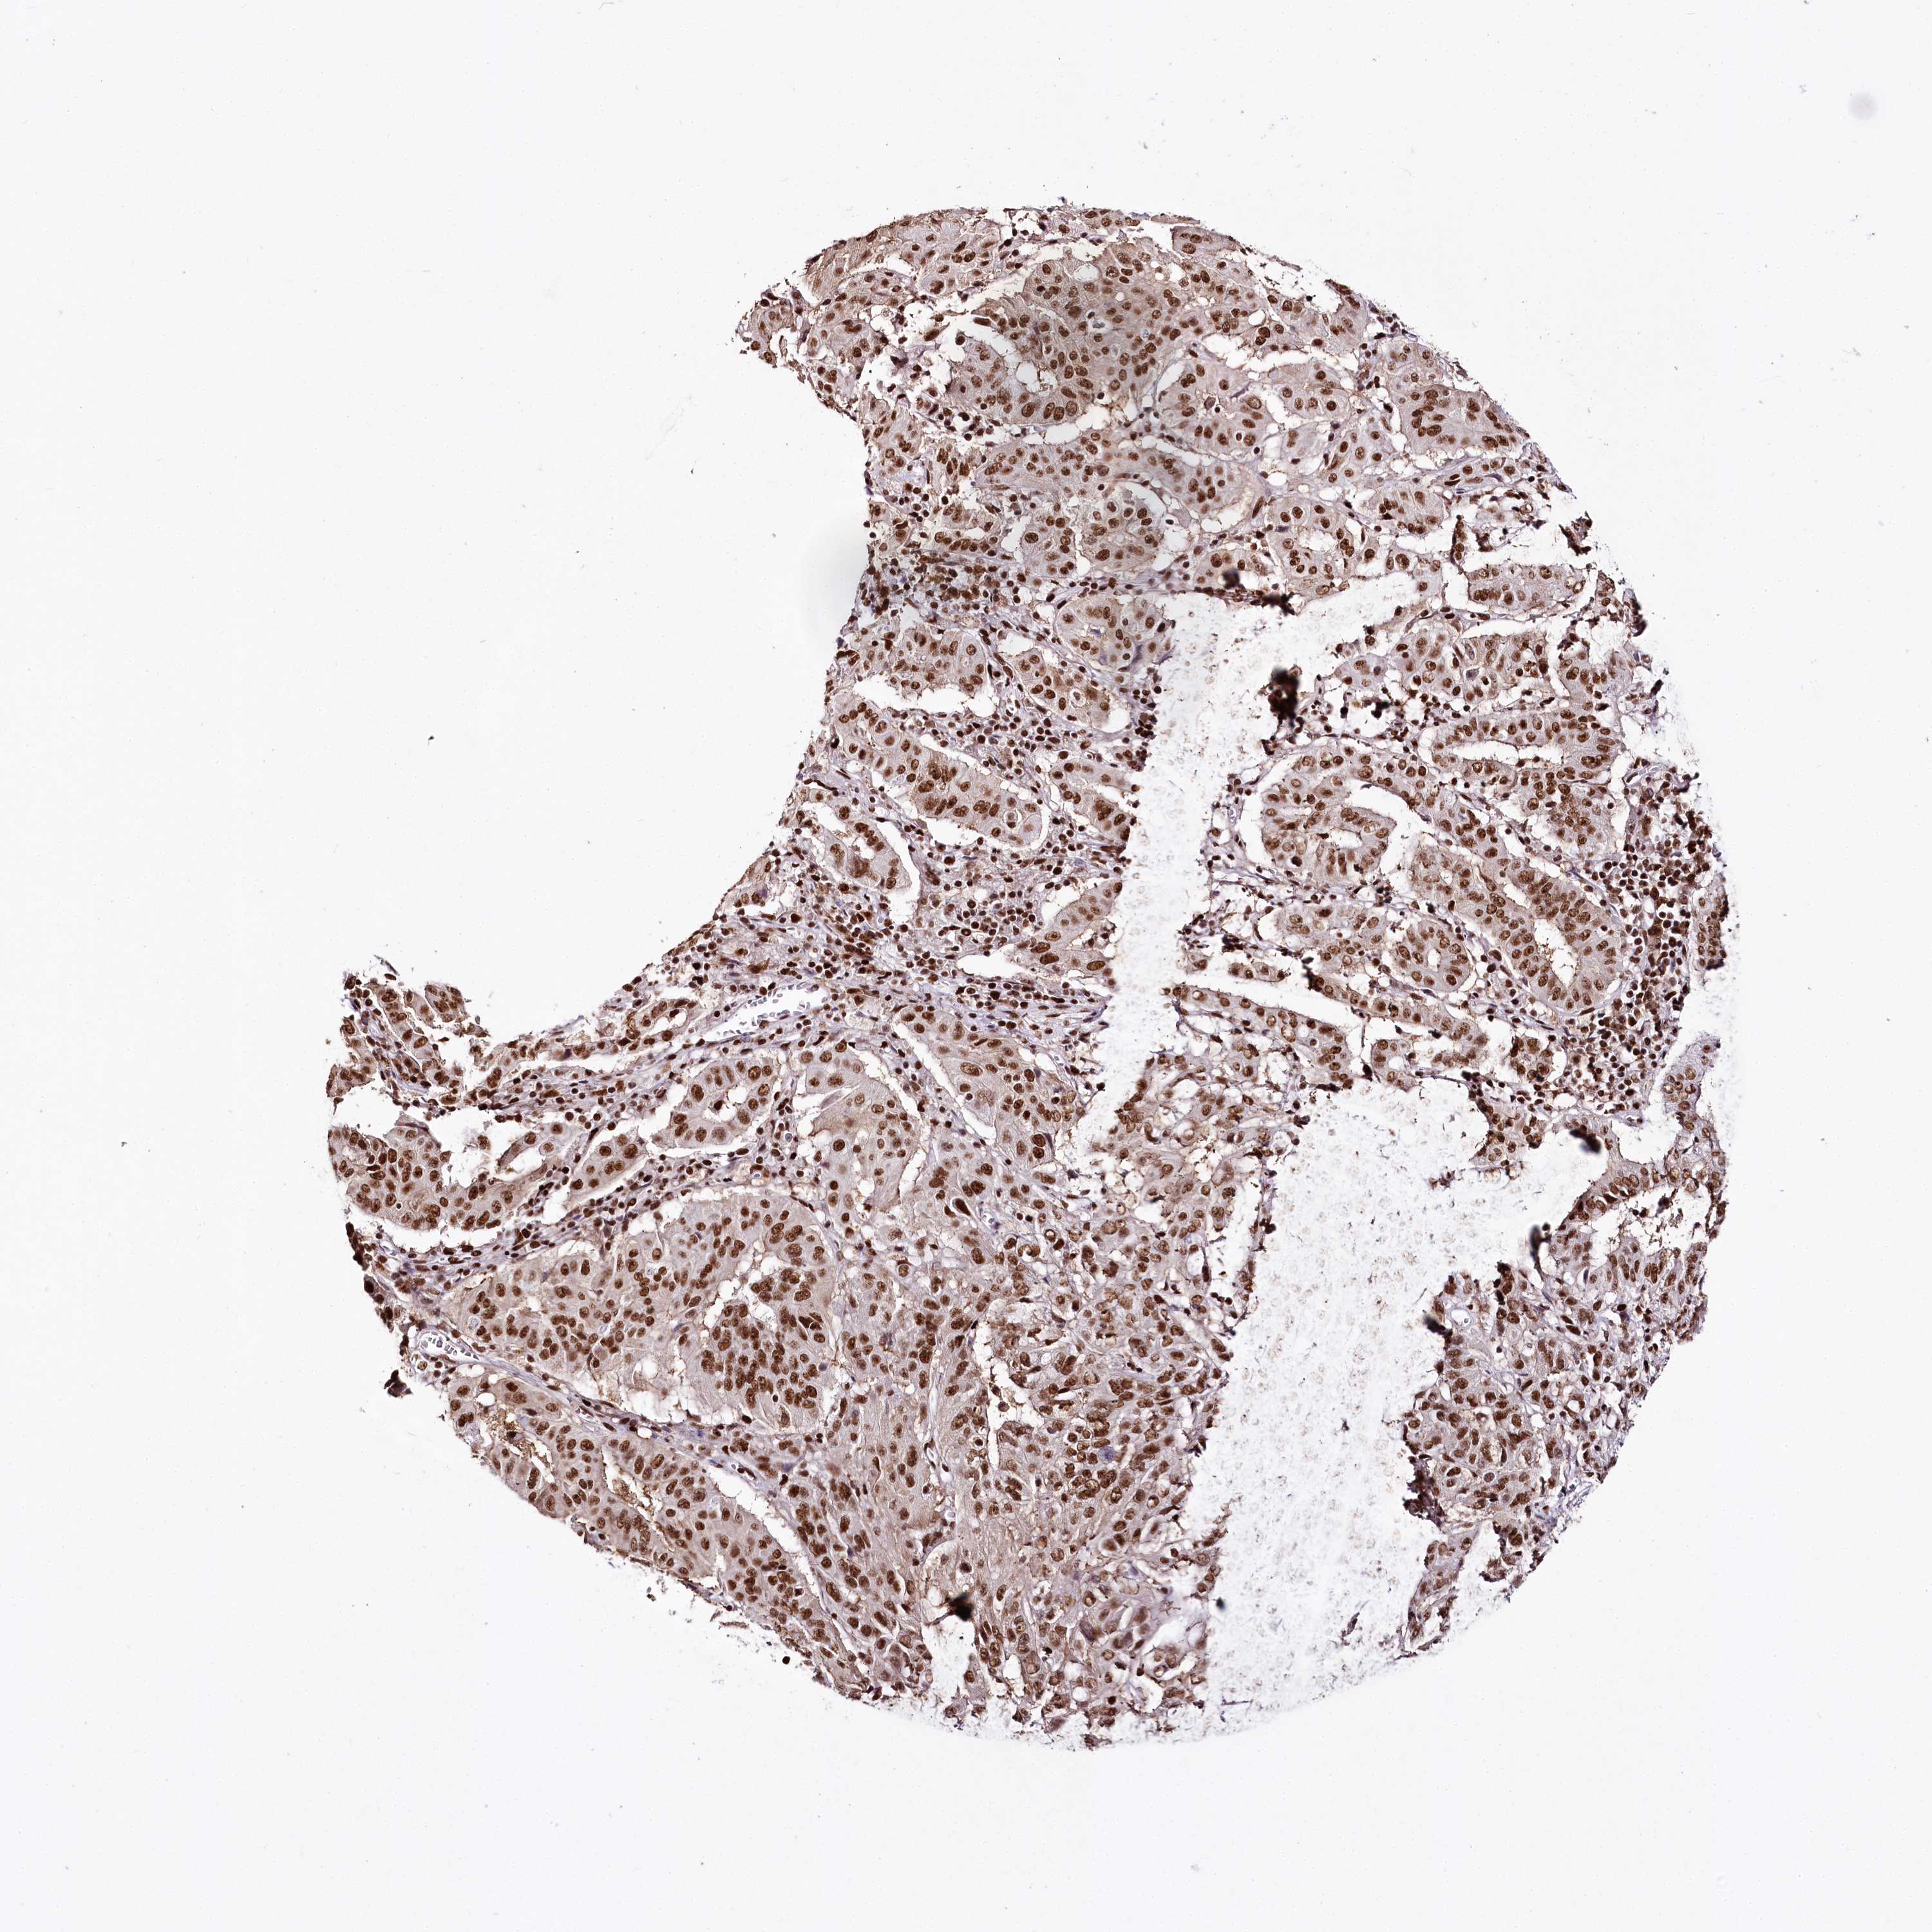

PANCREATIC CANCER - Protein expressioni

A mouse-over function shows sample information and annotation data. Click on an image to view it in a full screen mode. Samples can be filtered based on level of antibody staining by selecting one or several of the following categories: high, medium, low and not detected. The assay and annotation is described here.

Note that samples used for immunohistochemistry by the Human Protein Atlas do not correspond to samples in the TCGA dataset.

Antibody stainingi

Antibody staining in the annotated cell types in the current human tissue is reported as not detected, low, medium, or high, based on conventional immunohistochemistry profiling in selected tissues. This score is based on the combination of the staining intensity and fraction of stained cells.

Each image is clickable and will lead to virtual microscopy that enables deeper exploration of all samples and also displays staining intensity scores, fraction scores and subcellular localization as well as patient and tissue information for each sample.

Antibody HPA003916

Antibody CAB037318

Staining

High

Medium

Low

Not detected

Intensity

Strong

Moderate

Weak

Negative

Quantity

>75%

75%-25%

<25%

None

Location

Nuclear

Cytoplasmic/membranous

Cytoplasmic/membranous,nuclear

Adenocarcinoma, NOS

Adenocarcinoma, metastatic, NOS